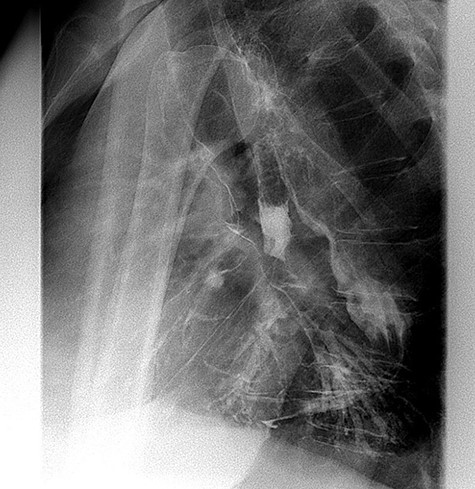

Lateral view of barium swallow demonstrating gastrobronchial fistula.